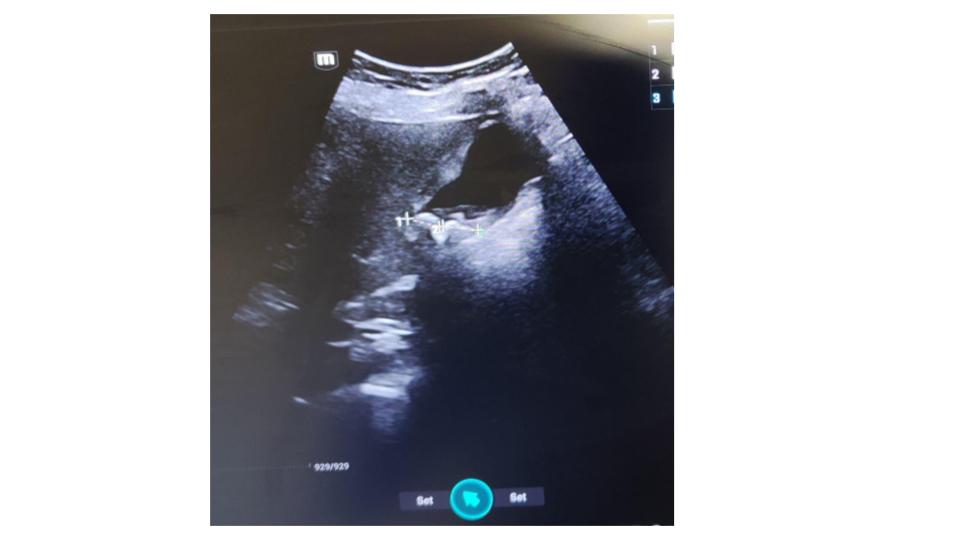

Ecografía a pie de cama con sistemática de exploración: Expansión anormal del conducto pancreático (conducto de wirsung), vía extrahepática con ligera dilatación sin imágenes patológicas en su luz. Vesícula biliar imágenes hiperecogénicas múltiples en su interior, que sugieren litiasis biliar y paredes vesicales engrosadas sin edema perivesicular.

La obstrucción pancreática es la causa principal de bloqueo en el flujo normal del jugo pancreático. Un wirsung que está dilatado por encima de 2 mm requiere evaluación más intensiva y tratamiento cuidadoso por alta sospecha de carcinoma pancreático.